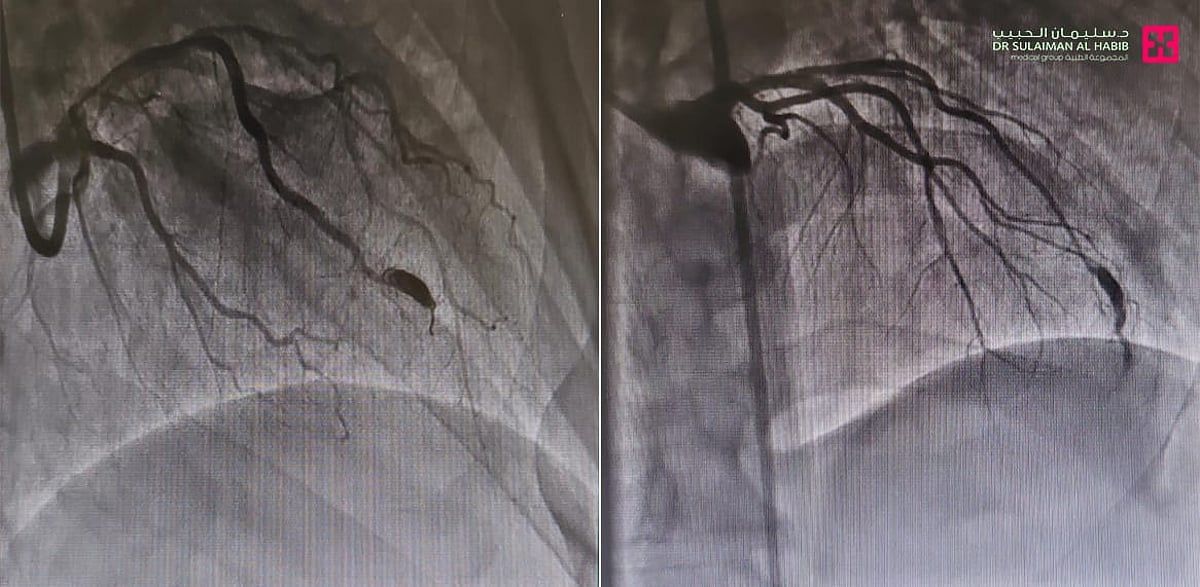

وقال د. فيصل الصميدي استشاري أمراض القلب وقسطرة الشرايين ورئيس الفريق الطبي المعالج، أن المراجع ظل يعاني منذ سنوات من ألم في منتصف الصدر، والإرهاق وحرقة المعدة والغثيان وضيق النفس، ومؤخراً تزايدت حدة هذه الأعراض، وأثرت على نمط حياته اليومية، فراجع المستشفى وأجريت له سلسلة من الفحوصات الطبية، كاختبار الجهد وتخطيط القلب والأشعة الصوتية، وقد أظهرت النتائج وجود انسدادات بالشرايين التاجية للقلب، ومن ثم خضع لقسطرة استكشافية أظهرت بدورها وجود توسع شديد في الشريان التاجي الأمامي، وسبب التوسع نقصاً في التروية في بعض أجزاء القلب، مما أثر على أجزاء معينة من عضلة القلب.

وتابع قائلاً أن الفريق الطبي قام بعد دراسة الحالة، ووضع خطة علاجية متكاملة تناسب حالة المراجع، وأجرى عملية متقدمة بتقنية القسطرة القلبية، تم فيها إزالة الانسدادات عن الشرايين التاجية، كما تم عمل إجراء طبي غير جراحي لسد التوسع الشديد في الشريان التاجي، عن طريق القسطرة التاجية "COILING" بالدخول عبر الشريان الفخذي، وتعمل هذه التقنية على سد التمدد ومنع تدفق الدم إليه، مما يقلل من خطر انفجاره، وهي تتميز بالفعالية العالية، ولا تتطلب شقوق جراحية كبيرة، وتجرى تحت التخدير الموضعي، إضافة إلى أنها أكثر أماناً وأقل مضاعفات مقارنة بالجراحة التقليدية.